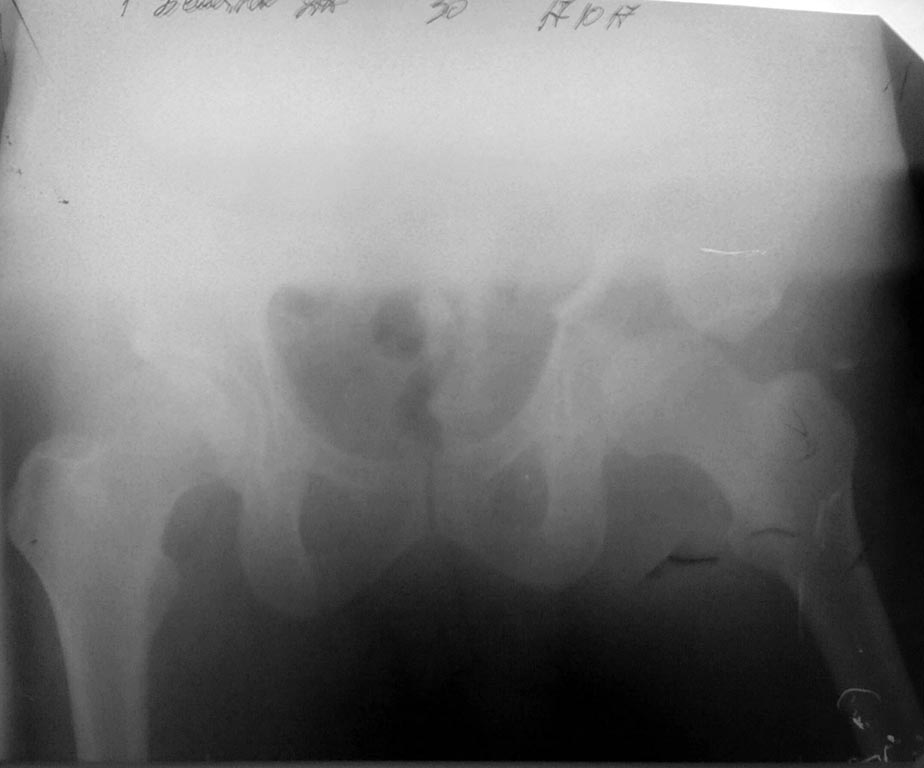

Это поперечный перелом вертлужной впадины, а не перелом таза.

И справа похоже тоже вертлужка сломанна .

Да, справа без смещения

Добрый день, уважаемые коллеги! Данный случай-полифокальное повреждение таза.Самый неблагоприятный вариант поперечно ориентированного перелома вертлужной впадины и ротационно нестабильное повреждение тазового кольца (КПС). Оперативное лечение- открытая реконструкция сустава и перкутанная фиксация КПС.

Вчера (17.10.17) снимок на месте палатным аппаратом.

Положение отломков прежнее.

Кт в день поступления прилагаю.